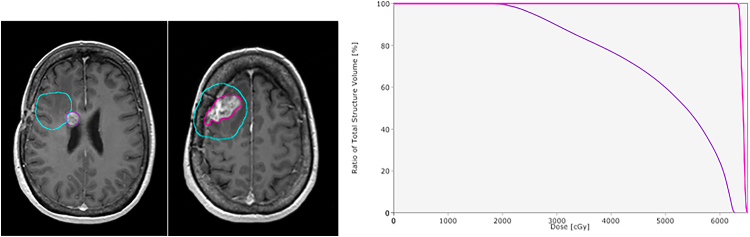

A case of a single recurrence with approximately 84% of the volume within 100% of the prescribed dose. In the first one, magnetic resonance imaging of tumor recurrence with the delineation shown in pink and the planning target volume in blue. In the second one, dose volume histogram showing approximately 84% of the volume of the recurrence within 100% of the prescribed dose.

Fig. 3.

A case of multiple tumor recurrences, with two different recurrence volume percentages within 100% of the prescribed dose. In the first one, magnetic resonance imaging of the first and second tumor recurrence. The delineation of first recurrence is shown in purple and the planning target volume (PTV) in blue. The delineation of second recurrence is shown in pink and the PTV in blue. In the second picture, dose volume histogram showing the recurrence percentages. The first shows approximately 25% of the volume of the recurrence within 100% of the prescribed dose and the second has >95%.